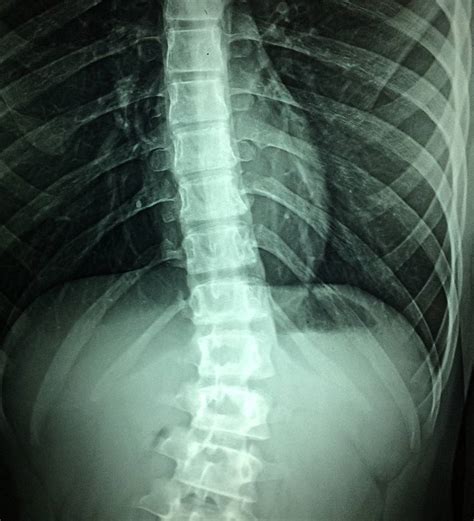

- Kifozė: Įgimta kifozė susijusi su embriono vystymosi sutrikimais, dėl kurių formuojasi patologinė stuburo kreivė. Kifozė ne tik sukelia skausmą, riboja judesius, bet, esant ryškiam išlinkimui, gali spausti krūtinės ląstą, sutrikdyti širdies ir plaučių veiklą.

- Skoliozė: Tai nenormalus stuburo išlinkimas ir pasukimas į šoną. Įgimta skoliozė - reta stuburo anomalija, kurią galima aptikti gimus.

- Rentgenografija: Naudojama vertinant mentės padėtį ir stuburo būklę, taip pat aptikti galimus slankstelių ar kitų kaulų anomalijas. Ji leidžia įvertinti stuburo kreivumo laipsnį, formą, atskleisti galimus patologinius pokyčius, pavyzdžiui, slankstelių deformacijas, tarpslankstelinių diskų aukščio pokyčius. Rentgeno nuotraukos atliekamos keliose projekcijose (iš šono ir priekio), kad būtų galima įvertinti trimačius stuburo pakitimus.